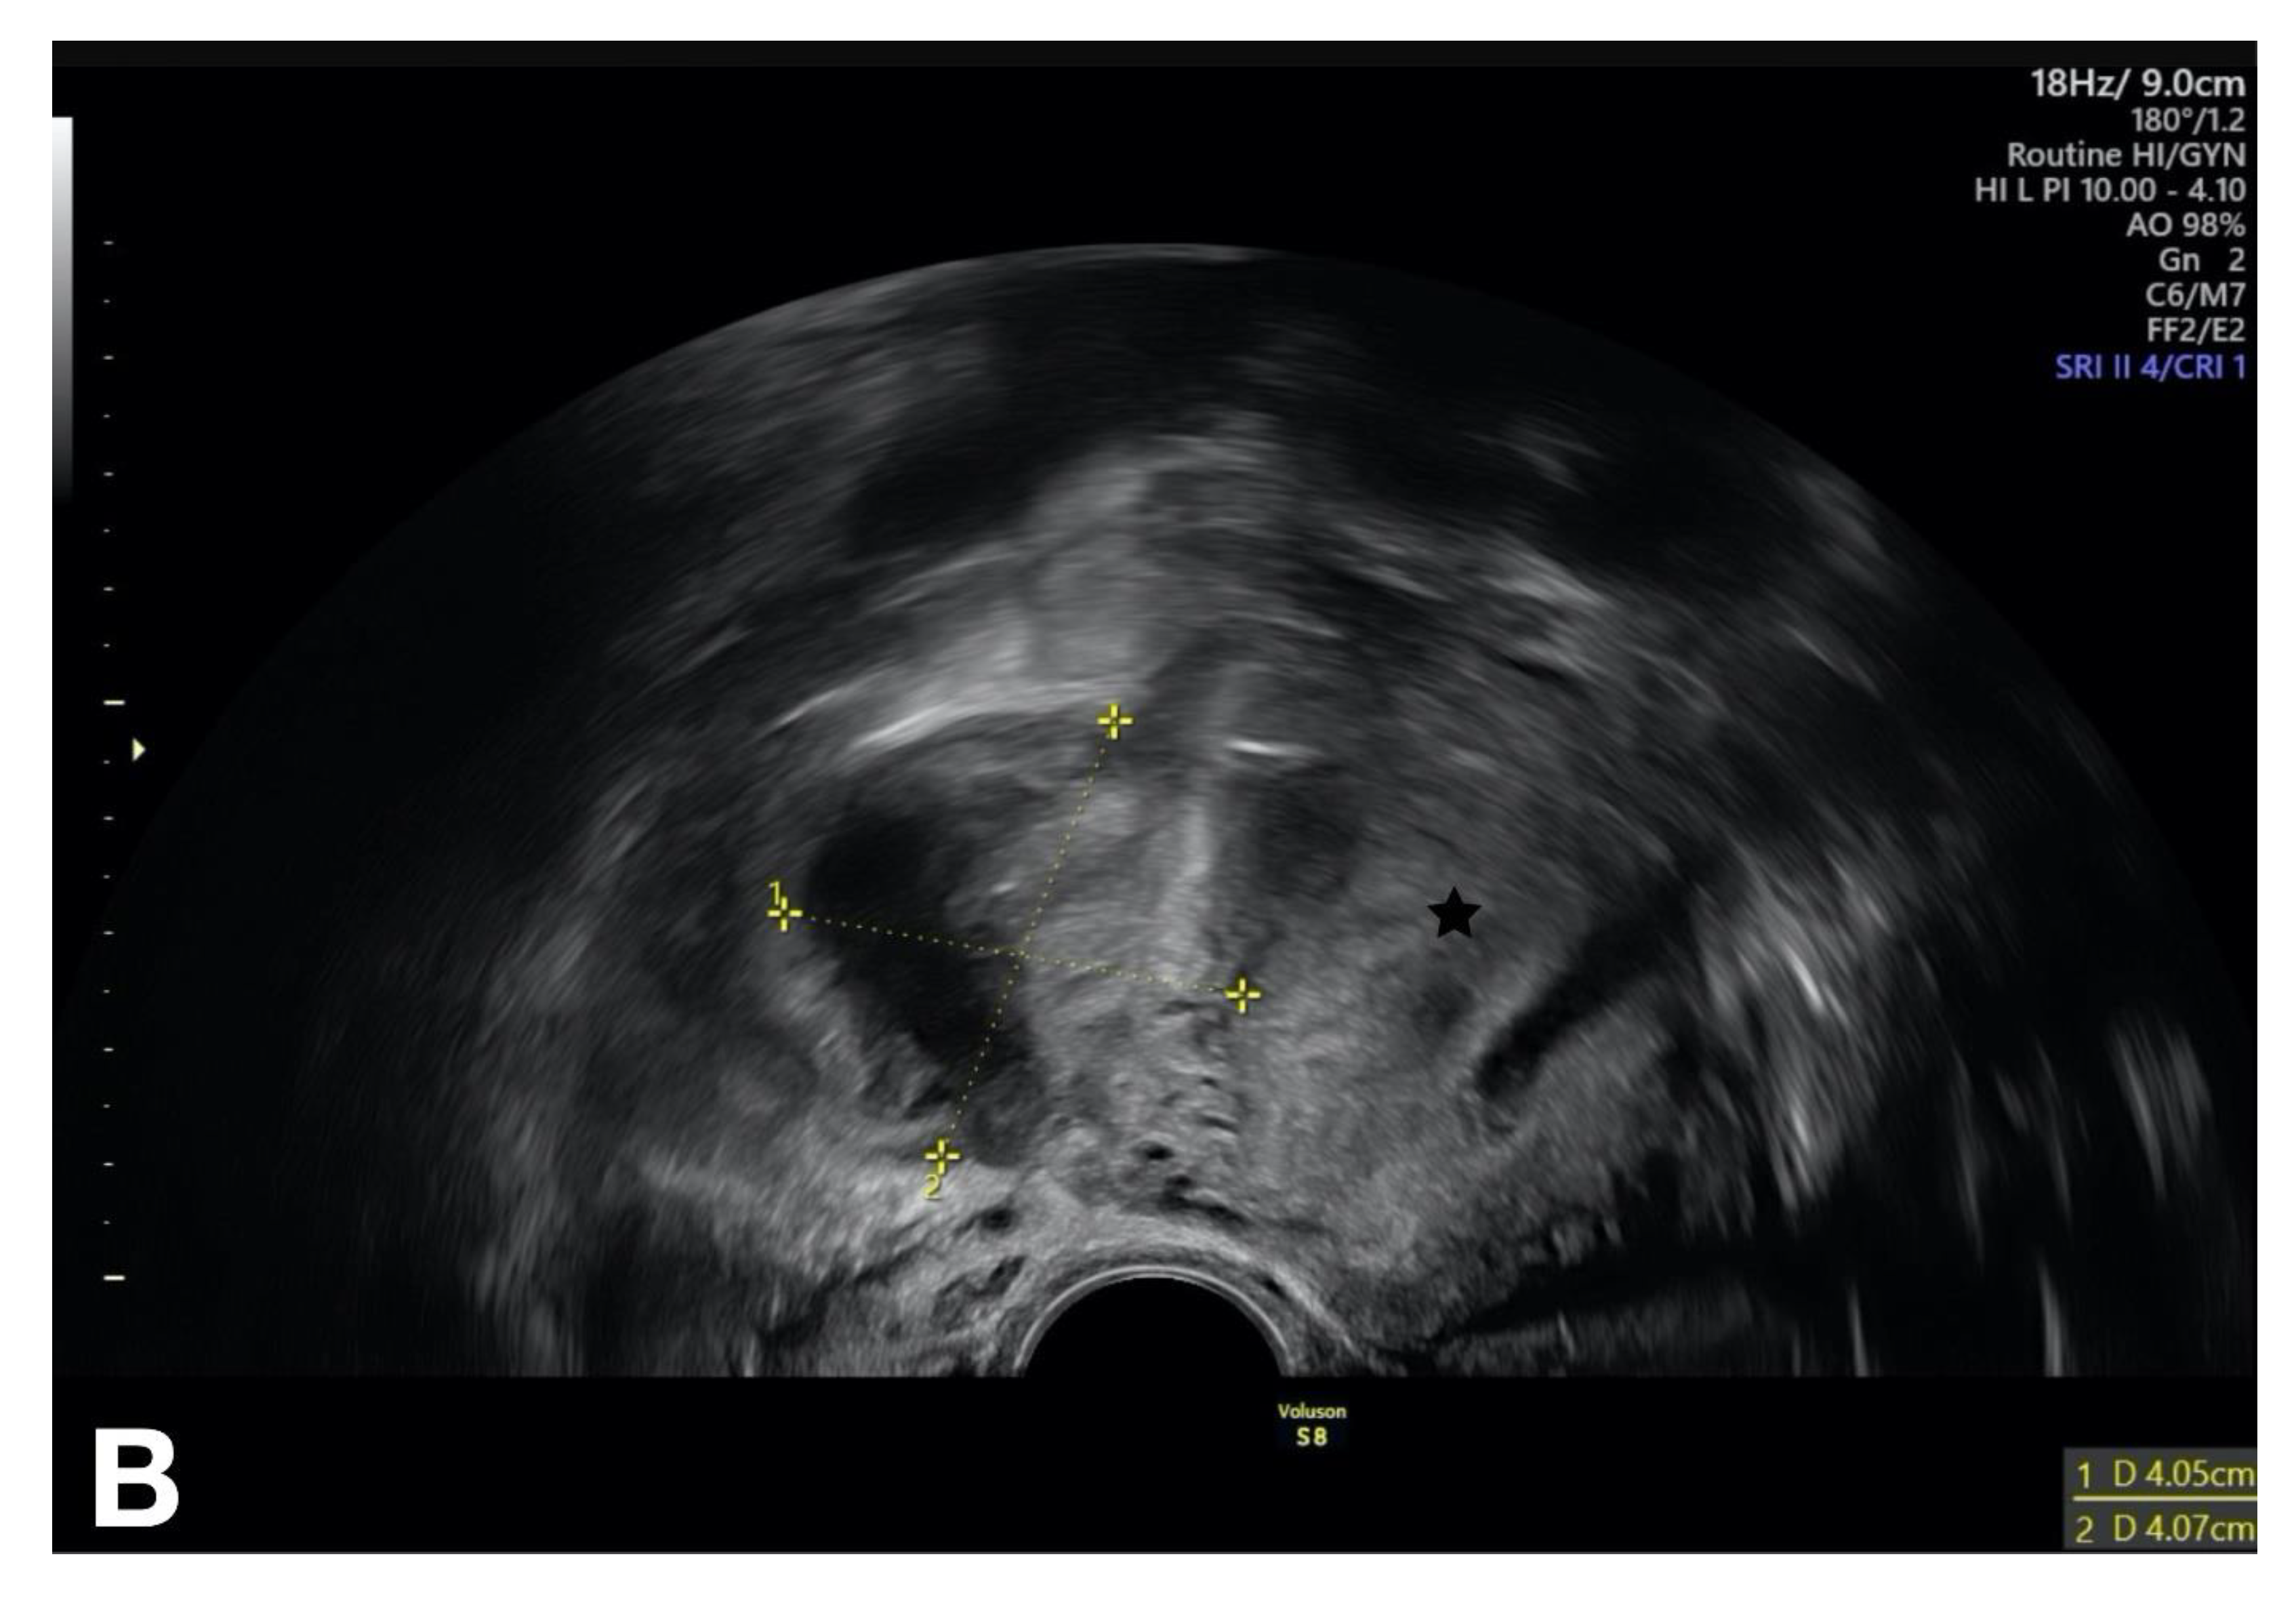

The patient reported above also had elevated inflammatory parameters. The vaginal ultrasound investigation, which was unpleasant for the patient, and the abdomen ultrasound investigation showed a thickened fallopian tube (>10 mm) on the right side. The Doppler investigation revealed increased vascularity. A hyperechogenic fluid was noted in the pouch of Douglas. We suspected a tubo-ovarian abscess on the right side as a complication of PID (Figure 8). We first initiated intravenous antibiotic therapy and then performed a secondary laparoscopy for drainage of the abscess after an interval of 3–4 days. Intraoperatively, we found a few adhesions; the right fallopian tube was adherent to the tubo-ovarian abscess. Therefore, we were unable to preserve the fallopian tube. In the region of the liver, we found adhesions to the abdominal wall by way of perihepatitis (Fitz-Hugh–Curtis syndrome). A surgical adhesiolysis is currently not recommended as a general measure because its value has not been clearly proven [36].

Figure 8.

Vaginal ultrasound investigation showing the tubo-ovarian abscess in the right-sided adnexa. The uterus is marked with a star [5].